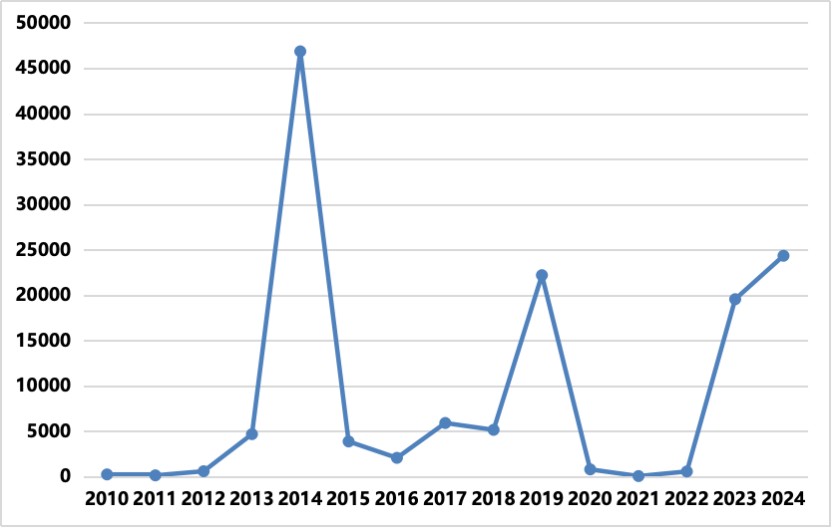

2008年,我國發(fā)現(xiàn)首例來自斯里蘭卡的基孔肯雅熱輸入性病例,2010年廣東省東莞市發(fā)生了我國首起基孔肯雅熱社區(qū)暴發(fā)。基孔肯雅熱在我國屬于輸入性傳染病,以零星輸入為主,尚未形成流行,因此我國居民對基孔肯雅病毒普遍易感,一旦蚊媒密度較高則極有可能發(fā)生該病的流行或暴發(fā)。

2010-2019年中國基孔肯雅熱病例報告數(shù)

登革熱在全球存在媒介伊蚊分布的熱帶、亞熱帶地區(qū)廣泛流行,累及全球100多個國家和地區(qū)。我國雖尚未形成穩(wěn)定的登革熱本地傳播疫源地,但輸入性病例常年可見。廣東、云南、福建、浙江、廣西、海南等多個省份曾多次發(fā)生輸入引發(fā)的本地傳播登革熱疫情,夏秋季高發(fā),各年齡段人群均可發(fā)病,以青壯年為主。

2010-2024年中國登革熱病例報告數(shù)